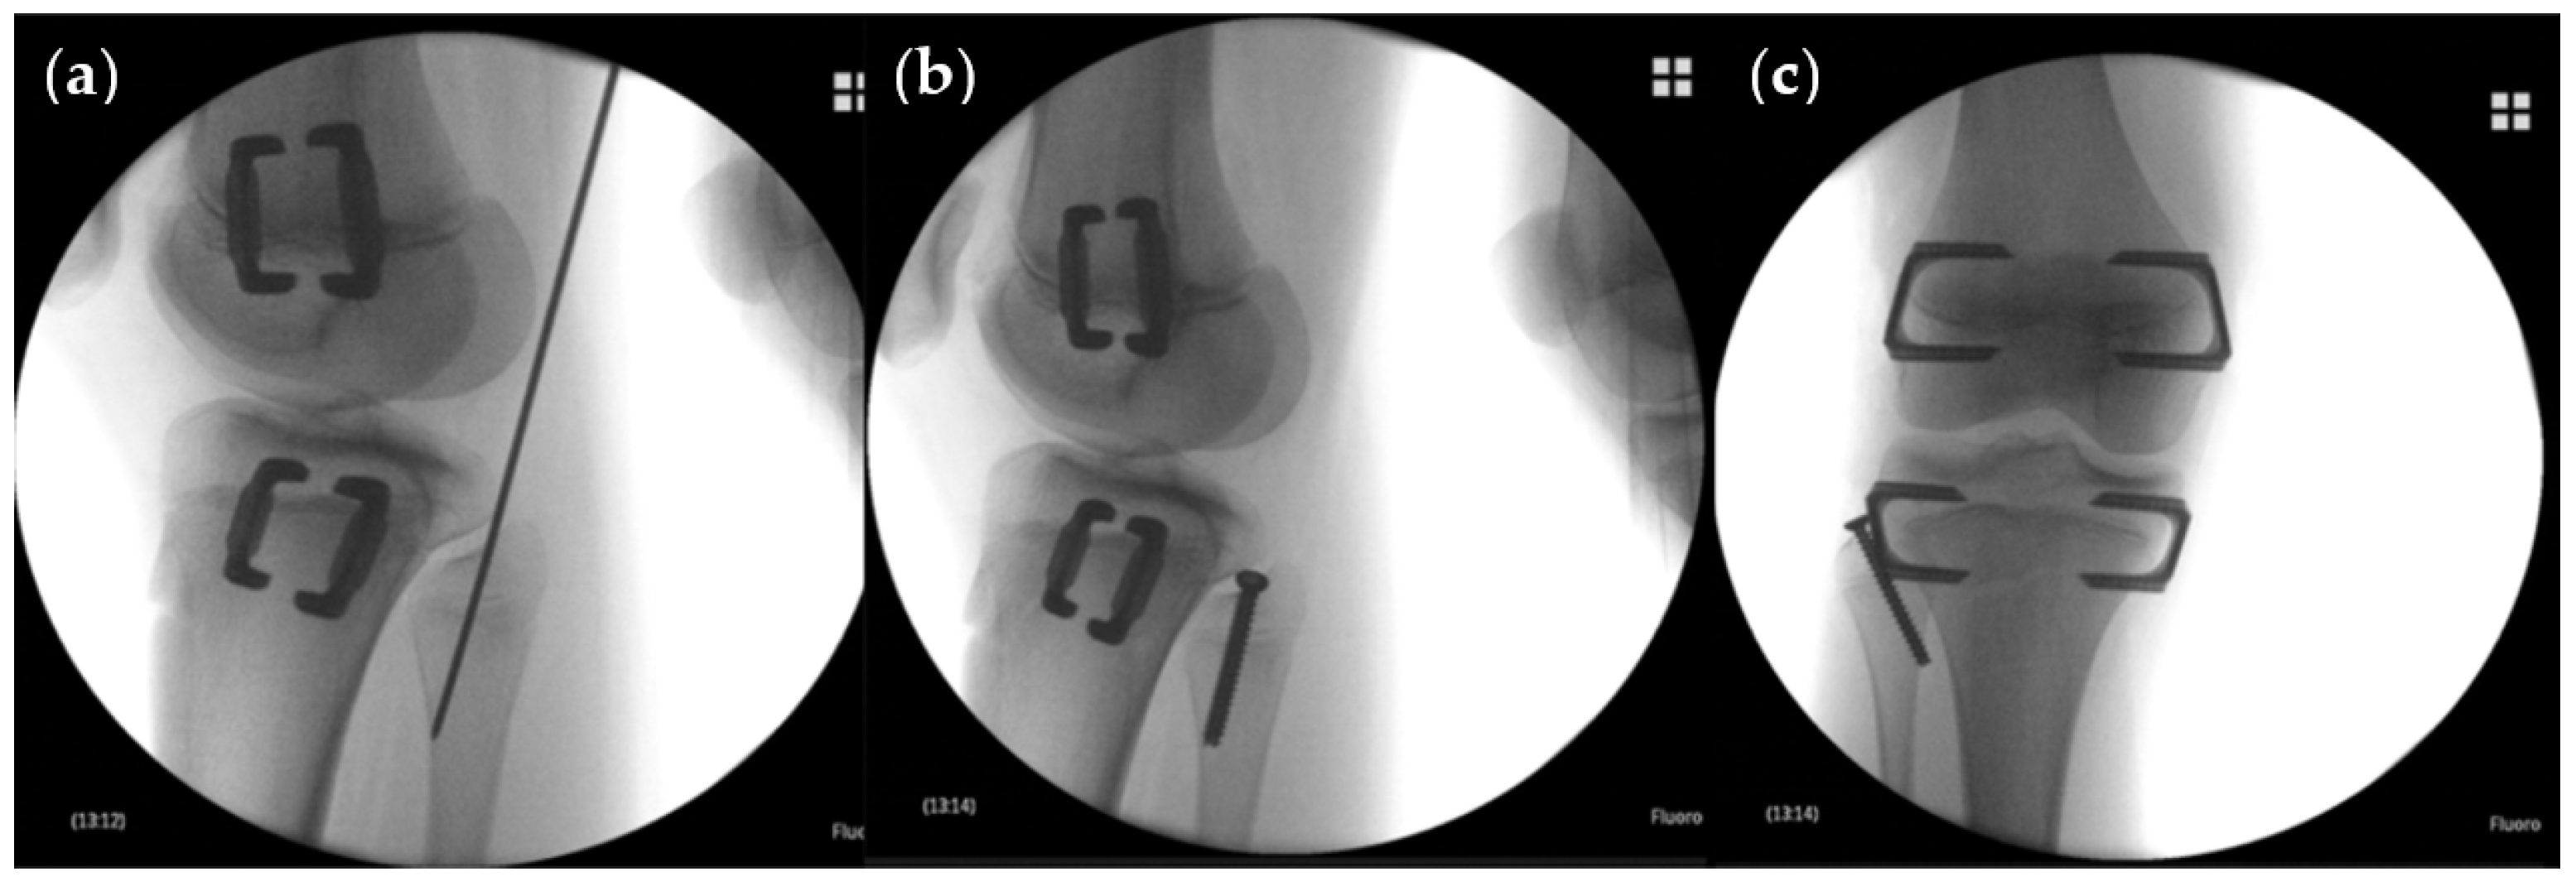

2.2. Indication, Operative Technique, and Applied Implants

2.3. Implants Applied for Epiphysiodesis